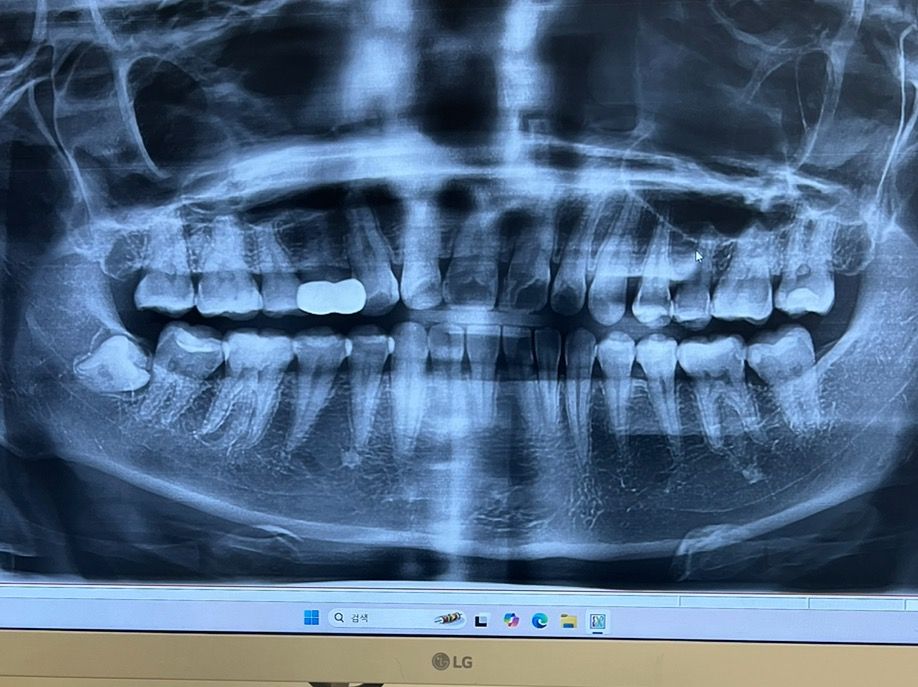

매복사랑니 언제 빼야되나요 ..??

일년정도 전부터 작게 보이기 시작했고 당시에 의사쌤이 뿌리도 안보이고 동네병원에서는 별말없이 아직은 뽑을때가 아니라고 하셨는데 째고 뽑는걸까요? 25세잉데 처음 난거라 ㅠ 지금이라도 사랑니 전문 병원가서 째고 뽑는게 좋을까요? 아님 언제까지 기다리는걸까요

사진으로 봤을 경우에는 사랑니가 완전히 매복이 되어 있고 주변조직에 문제를 발생시키지 않는것으로 보입니다.

따라서 굳이 발치를 할 필요는 없을것으로 생각됩니다.

1. 기다려도 맹출 안합니다 옆 어금니에 걸려있습니다

2. 뺀다면 한살이라도 젊을때 빼는게 발치 더 수월합니다

불편하시면 당장 발치를 하시는게 좋지만 완전 매복 사랑니라 무조건 발치를 하실필요는 없을것같습니다.